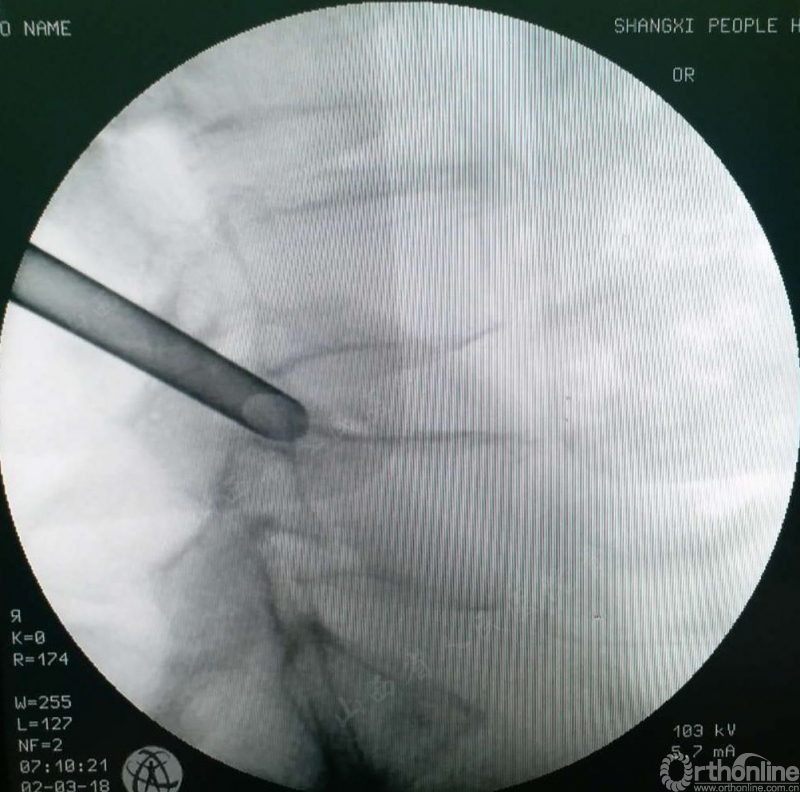

第二步:逐步行软组织扩张,无需盲视下行椎间孔成型,直接置入工作通道,只需要侧位片判断工作通道置入椎间孔区即可,明显减少手术步骤和透视次数。如图2

图2 工作通道置入椎间孔区